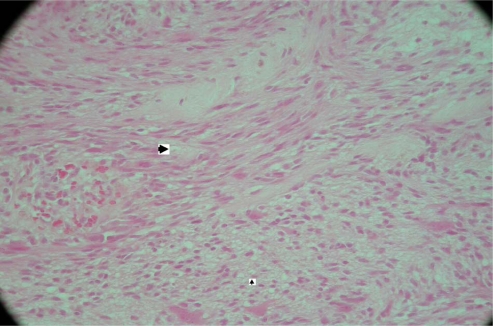

Fig. 1.

Histological examination reveals a tumour composed of schwann cells, which are seen as streams of elongated cells with tapering nuclei. Two main patterns of cellular organisation are clearly seen in this case. The compact areas where cells are arranged in streams (Antoni A)—marked by bigger arrowhead. The smaller arrowhead marks loosely arranged cells with areas of vacuolation and lipidisation (Antoni B). Elsewhere, blood vessels show thickening and hyalinisation of their walls. Mitoses are sparse and the appearances are of a conventional Schwannoma (WHO grade I) (case 1)